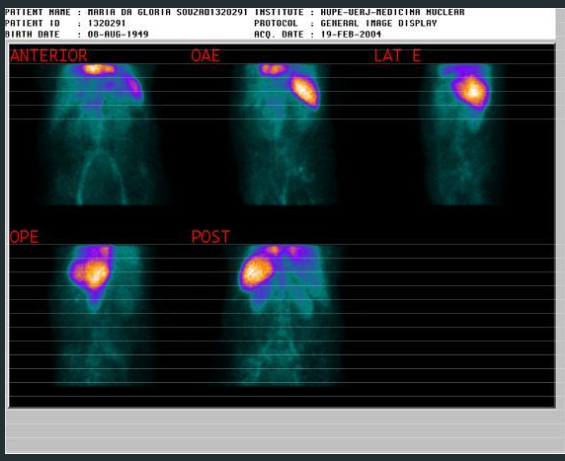

CINITOLOGRAFIA ESPLÊNICA

1.VERIFICAR HIPERESPLENISMO OU BAÇO ECTÓPICO